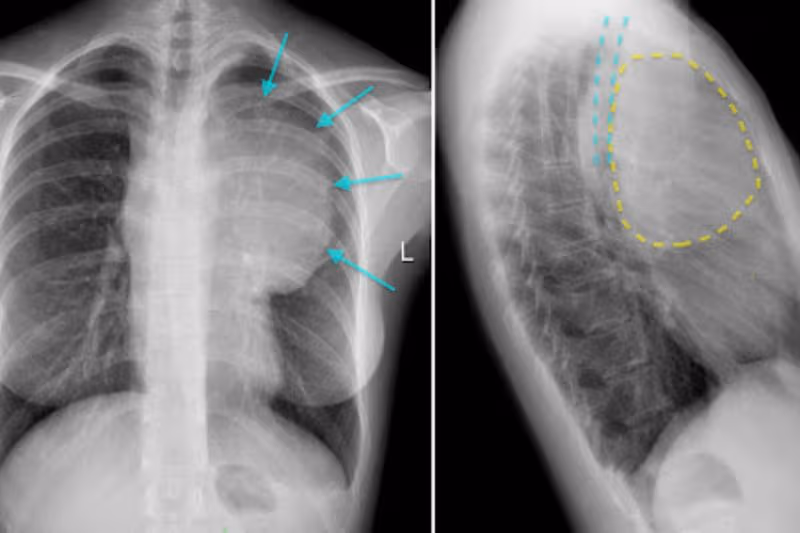

1. Xác định vị trí u trung thất ở diện thẳng

U trung thất có thể lành tính hoặc ác tính, tùy thuộc vào bản chất của khối u. Trên phim chụp X quang, trung thất thường được phân chia thành ba tầng theo chiều đứng:

– Tầng trên: nằm phía trên quai động mạch chủ.

– Tầng giữa: kéo dài từ dưới quai động mạch chủ đến chỗ chia đôi khí quản.

– Tầng dưới: tính từ đó trở xuống đến vòm hoành.

3.1. Dấu hiệu bóng mờ khi chụp X quang u trung thất

Trên phim X quang, các khối u thường xuất hiện dưới dạng hình ảnh “bóng mờ”. Bác sĩ sẽ dựa vào vị trí của bóng mờ so với bờ tim để xác định vị trí khối u. Nếu hình mờ làm mất ranh giới tim, khả năng cao khối u nằm ở trung thất trước hoặc thùy giữa/lưỡi của phổi. Nếu bóng mờ chồng lên tim nhưng không xóa bờ, vị trí thường ở trung thất sau hoặc thùy dưới phổi.